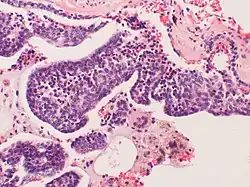

Pulmonary neuroendocrine cells (PNECs) are specialized airway epithelial cells that occur as solitary cells or as clusters called neuroepithelial bodies (NEBs) in the lung. Pulmonary neuroendocrine cells are also known as bronchial Kulchitsky cells.[2] They are located in the respiratory epithelium of the upper and lower respiratory tract. PNECs and NEBs exist from fetal and neonatal stages in the lung airways.

These cells can be the source of several types of lung cancer, most notably small cell carcinoma of the lung, and bronchial carcinoid tumor.[3][4]